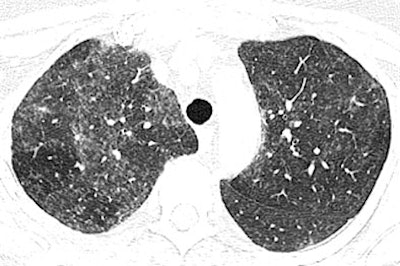

| High-resolution CT image through lungs at level of bronchus intermedius in 54-year-old woman shows nodular areas of ground-glass attenuation with centrilobular distribution bilaterally. Image republished with permission of the American Roentgen Ray Society©, from AJR 2007; 188:1050-1053 by Thomas E. Hartmann, Eric Jensen, Henry D. Tazelaar, Viktor Hanak, and Jay H. Ryu. |

In the new pattern of pulmonary disease known as hot tub lung, "centrilobular nodules and areas of ground-glass attenuation are the most common findings, and typically have diffuse but patchy distribution throughout both lungs," Hartman and colleagues wrote. Expiratory images showed evidence of air trapping in all seven cases for which they were available, they added.